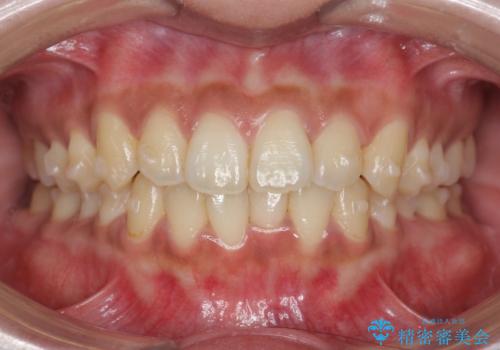

前歯のがたつきをすっきり マウスピース矯正

- 長年気になっていた前歯のがたつきをマウスピース矯正で治したい!と希望され来院されました。

奥歯の噛み合わせには問題がなく、前歯のがたつきの改善のみで十分に審美的な結果が得られるため、ワイヤーではなくマウスピース矯正での治療を計画します。

しっかりと前歯のがたつきは改善し見た目が大きく良くすることができました。